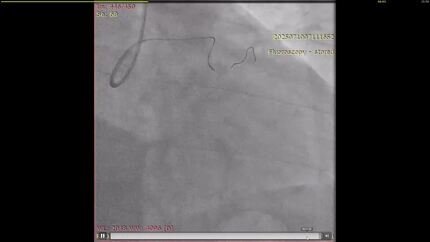

Snaring a protruding aorto-ostial coronary stent: A novel anchoring technique for facilitating antegrade treatment of a chronic total occlusion